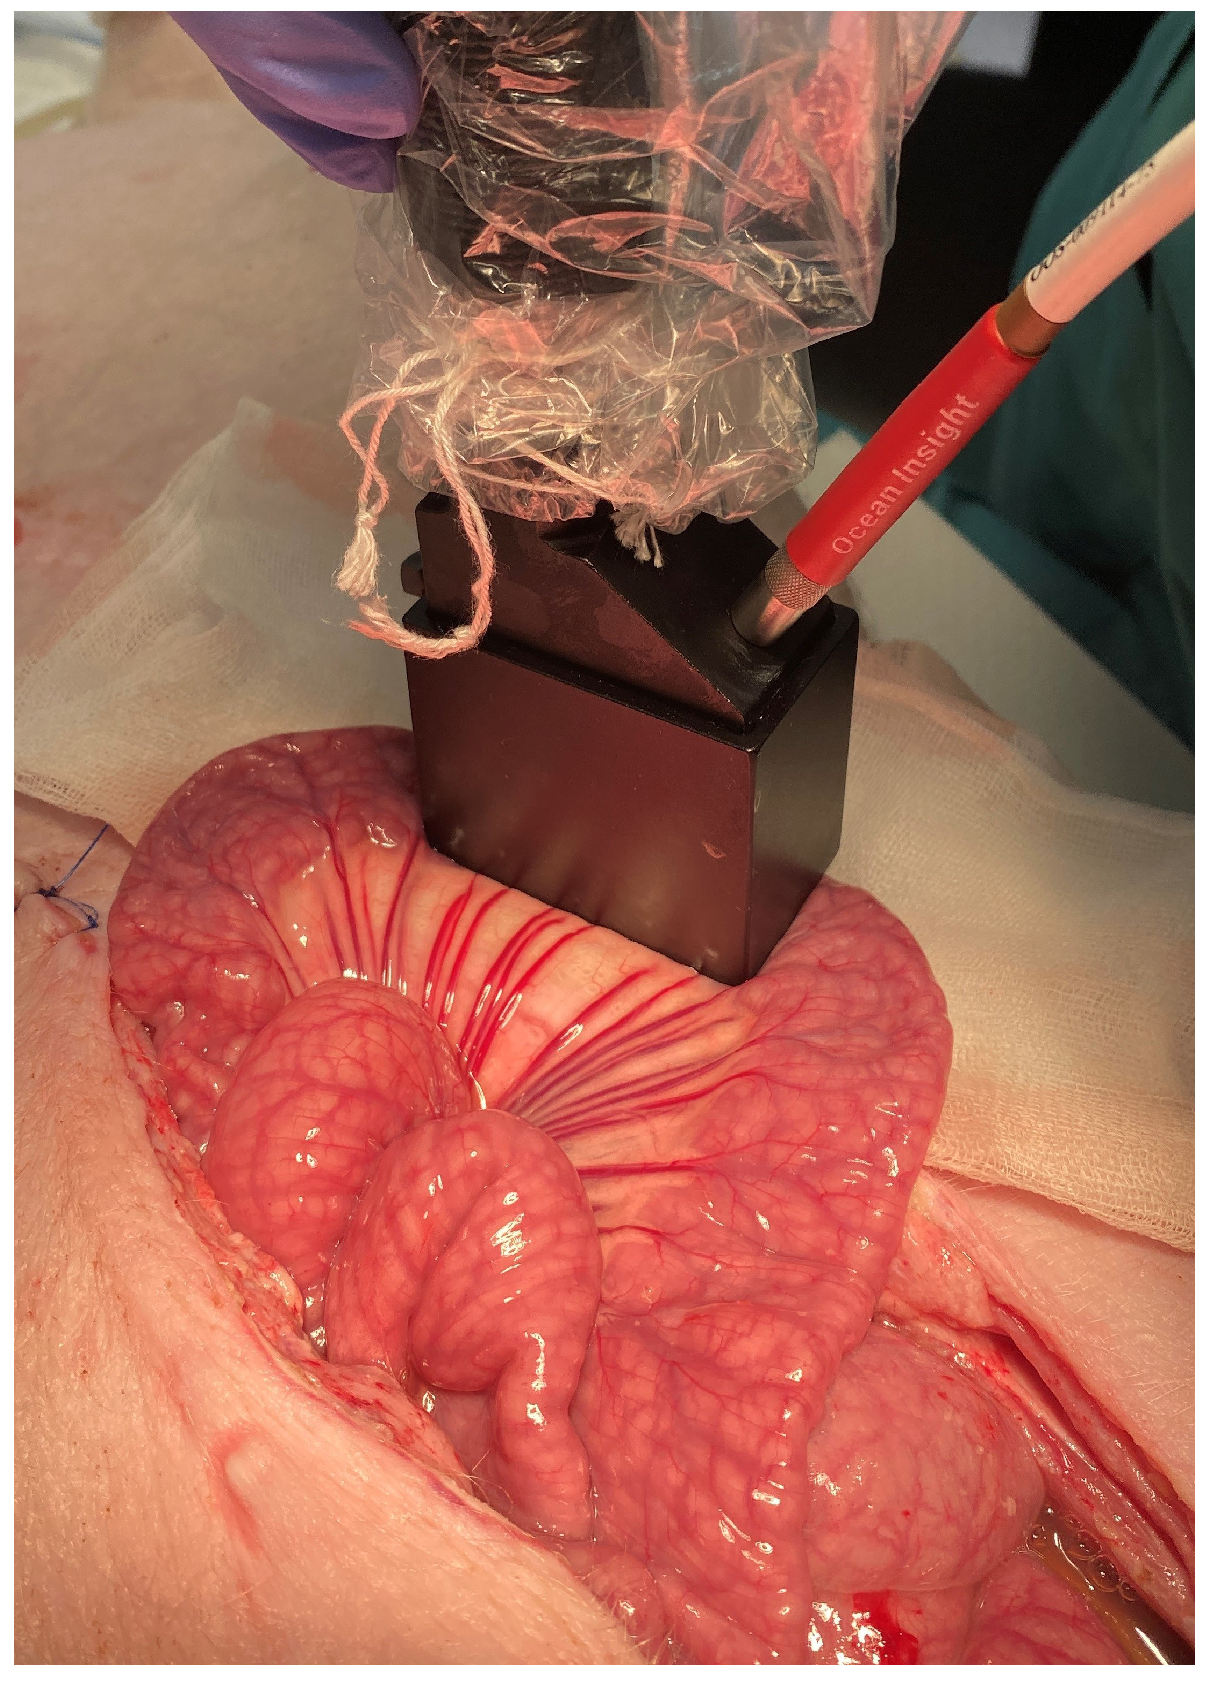

2.2. Visible and Near-Infrared Diffuse Reflectance Spectroscopy Setup